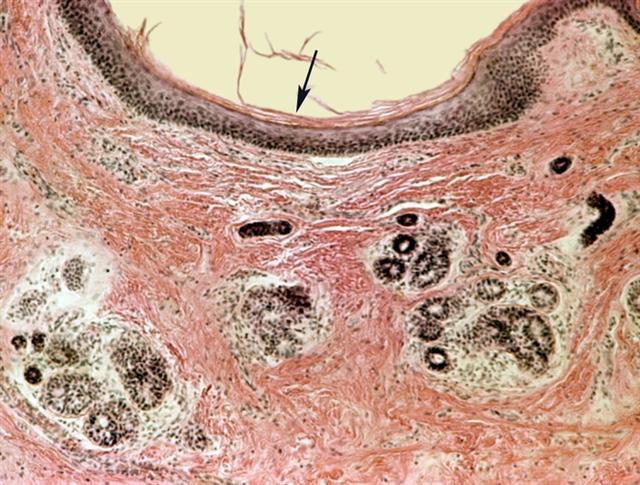

Рис. 1. Микропрепарат стенки дермоида: внутренняя поверхность кисты покрыта многослойным плоским ороговевающим эпителием (указан стрелкой), в толще стенки среди грубоволокнистых прослоек соединительной ткани расположены группы желез (придатки кожи); окраска гематоксилином и эозином; ´80. |